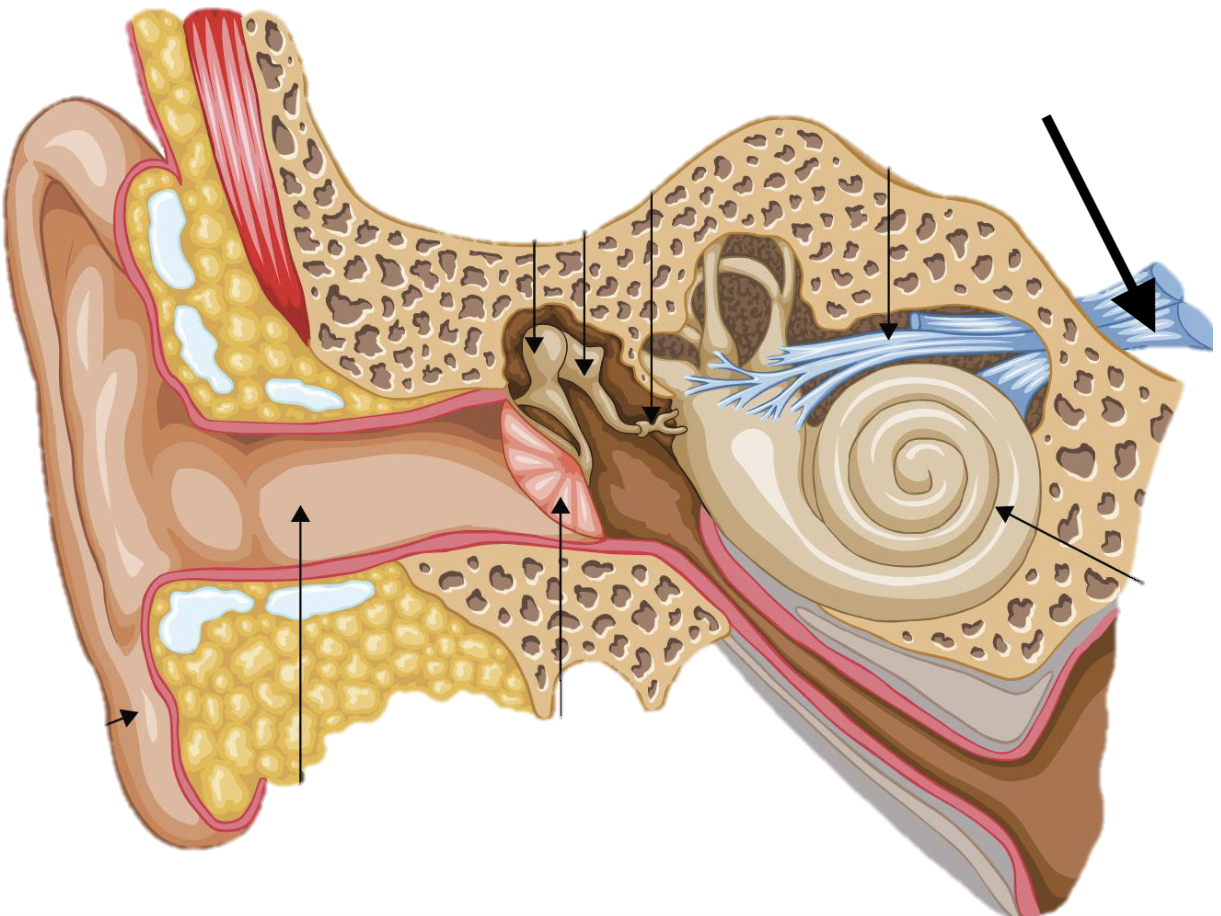

Name the feature of the ear ossicle

External acoustic meatus

Name the feature of the ear ossicle

Malleus

Name the feature of the ear ossicle

Incus

Name the feature of the ear ossicle

Stapes

Name the feature of the ear ossicle

Internal acoustic meatus

Name the feature of the ear ossicle

Cochlea

Name the feature of the ear ossicle

Temporal bone